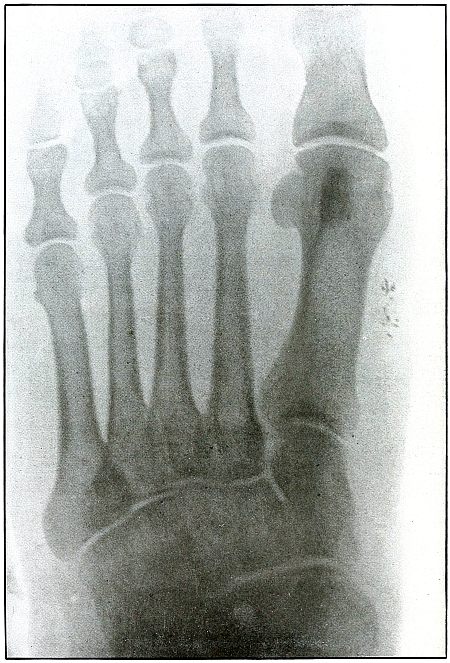

154. Gunshot wound, foot 318

155. Gunshot wound, foot 320

156. Gunshot wound, foot, multiple 322